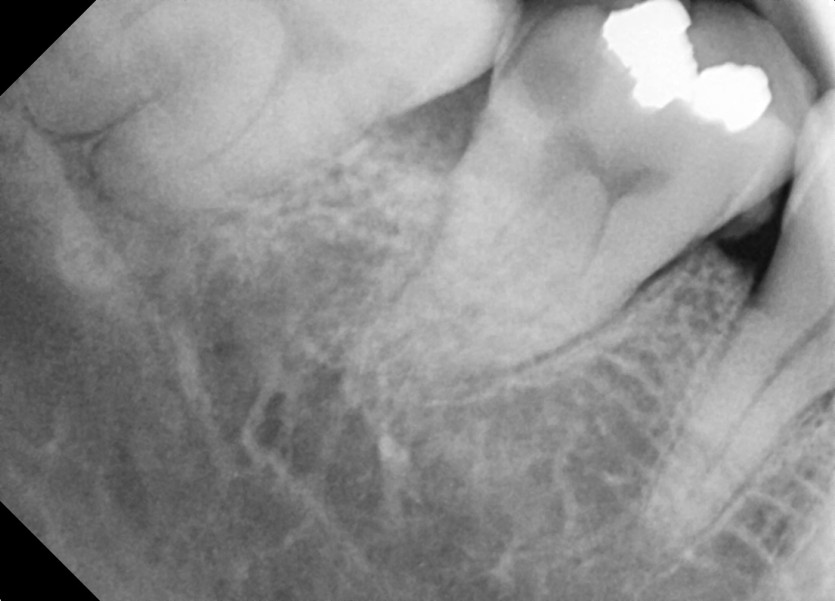

#48 사랑니 발치

구강 외과 전문의가 당일 발치했습니다.